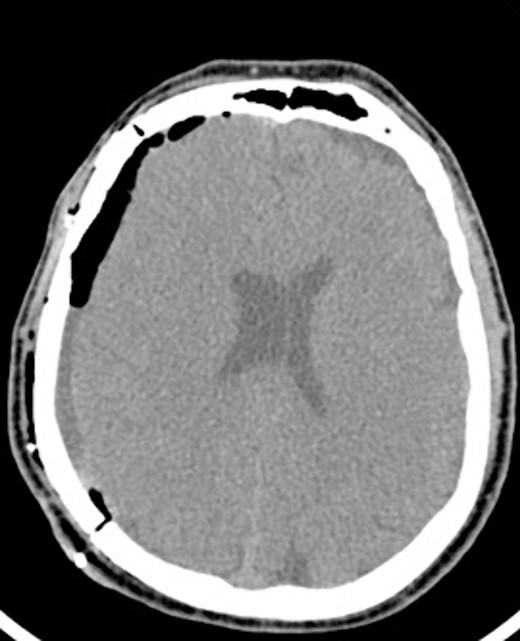

A 60-year-old male with cSDH presented to a Level I trauma center with lethargy, headaches, and left-sided hemiparesis. CT demonstrated thickened membranes and midline shift (Fig. 1).

An AR system was used to register the patient’s 3D anatomy onto the patients’ head (Fig. 2). Burr hole locations were annotated onto the registered 3D model to assist with craniotomy planning. Visualization of the 3D model confirmed plans for safe burr hole placement away from the dural venous and bony sinuses for a right frontoparietotemporal craniotomy. The AR headset was used once again to visualize the hematoma, vascular structures, and to confirm proper burr hole locations. The evacuation of the subdural hematoma was performed. Eight burr holes were placed, and a 14 × 11 cm bone flap was elevated to access the dura. The dura was then opened in a curvilinear fashion and hinged over the superior sagittal sinus. The cSDH was identified by its thick parietal and visceral membranes and underlying liquefaction, and these anatomic layers correlated directly with the AR overlay. The membranes of the hematoma were resected with the cortex demonstrating no gross abnormalities. The wound was irrigated, and the dura was closed primarily. The bone flap was then secured with two central tack-up structures followed by titanium reconstruction with multiple burr hole covers. There were no intraoperative complications, and the patient tolerated the procedure well with improved strength and decreased headache postoperatively. Post-operative CT showed interval decrease in the mixed-density subdural collection and reduced midline shift (Fig. 3).